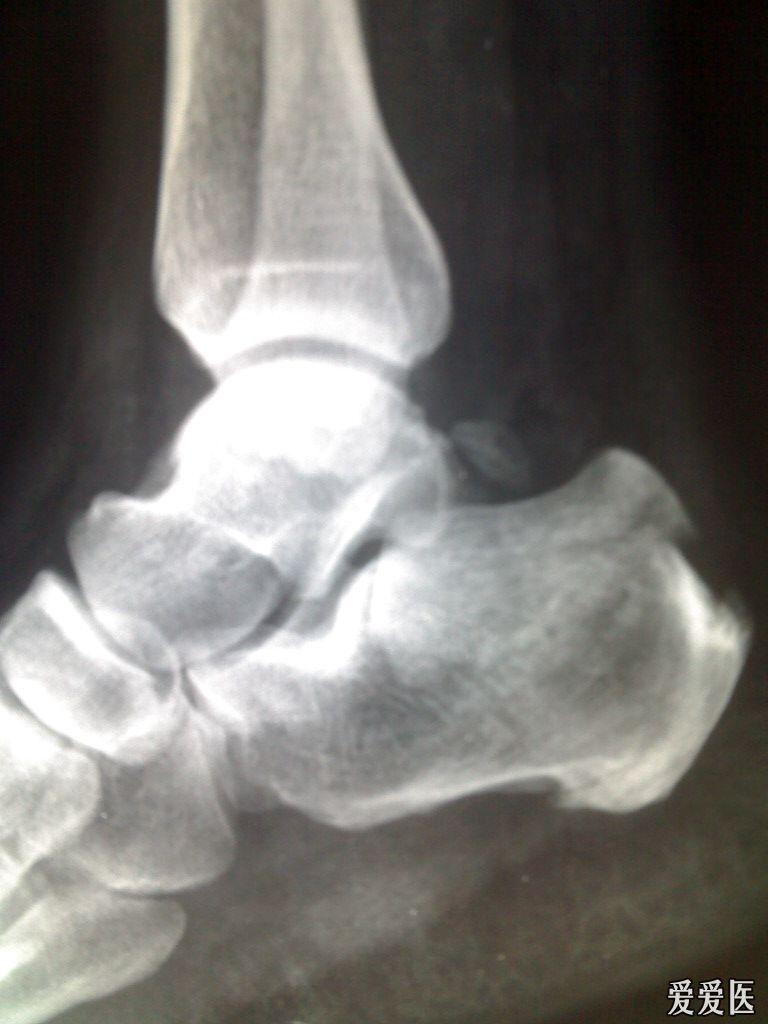

正常跟骨x片,正常跟骨清晰图片

正常跟骨清晰图片

足跟骨正常x片

正常跟骨x线解剖图片

正常脚跟骨x光片

正常脚跟骨x光图片

正常跟骨x片影像图片

跟骨x片

正常的足跟骨x片